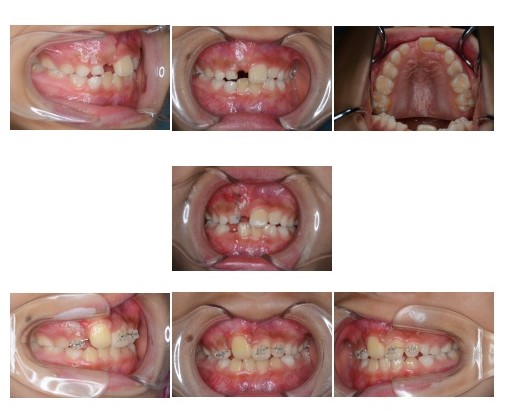

埋伏歯(歯が生えてこない)

主訴:前歯がはえてこない

診断名:上顎右側中切歯埋伏

年齢:8歳

装置名:マルチブラケット装置 リンガルアーチ

治療費(施術料 装置料 調整料): 25万(税込み)

治療期間:6か月

考えられるリスク:矯正歯科治療に伴う一般的なリスク

(歯根吸収、虫歯、歯周病、歯の移動時の痛み、牽引する歯の歯肉退縮、歯の癒着)